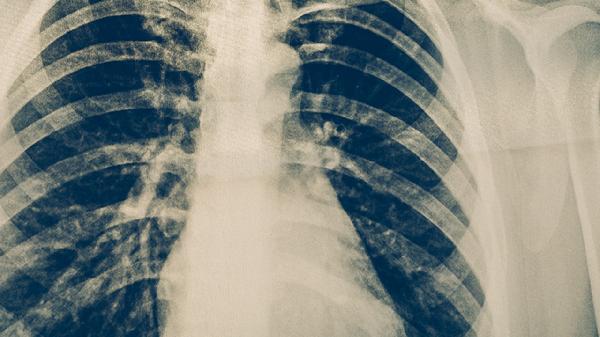

肺癌早期治愈率相对较高,积极治疗有助于改善预后。早期肺癌通常指肿瘤局限在肺部且未发生转移的阶段,治疗效果与肿瘤类型、患者身体状况及治疗方式等因素有关。

早期肺癌患者在接受规范手术后,五年生存率可达到较高水平。肿瘤体积较小且未侵犯周围组织的患者,预后更为理想。手术治疗能够完整切除病灶,术后根据病理结果可能需要辅助化疗或靶向治疗。采用胸腔镜微创手术的患者恢复较快,术后配合肺功能锻炼有助于减少并发症。定期复查胸部CT可以及时发现异常情况。

部分早期肺癌患者因心肺功能较差无法耐受手术,可采用立体定向放射治疗。这种精准放疗技术能有效控制肿瘤进展,对周围正常组织损伤较小。对于携带特定基因突变的患者,术前新辅助靶向治疗可使肿瘤缩小,为手术创造更好条件。免疫治疗也在早期肺癌综合治疗中发挥重要作用。